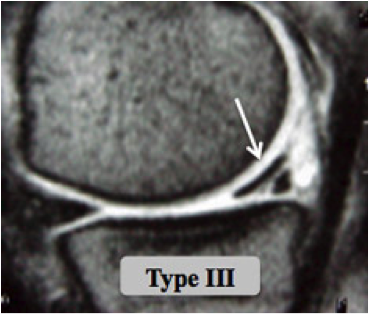

Des examens plus spécifiques comme l'IRM et l'arthroscanner sont demandés si les radiographies sont normales; ils vont permettre de visualiser les structures ménisco-ligamentaires et cartilagineuses de l'articulation.